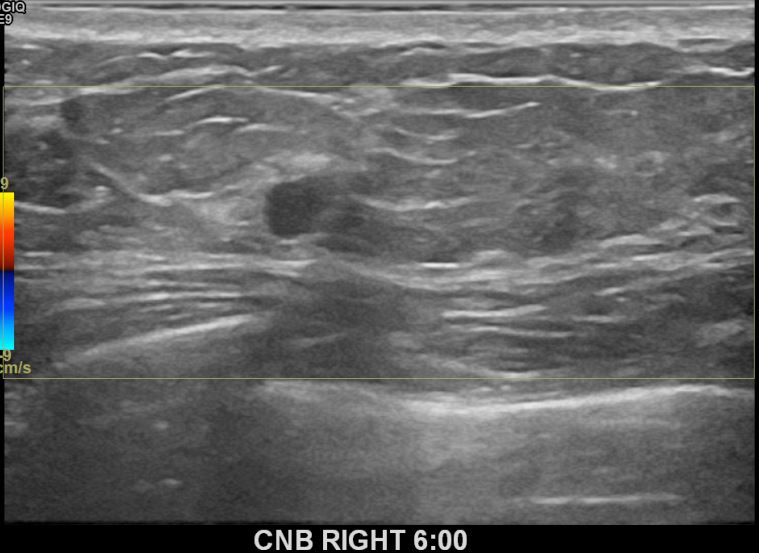

상기환자는 외부검사이상소견으로 내원하신 40대중반

여성분으로 의심스러운 우측혹 조직검사 시행해 침윤성암 으로 진단되었습니다